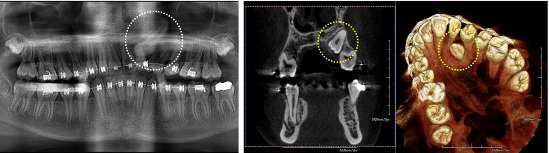

Case2: Maxillary impacted canine tooth

Slight shadow can be seen in the panoramic image. In the 3Dimage (MPR:Cpronal), the state of the eruption and the position of the maxillary impacted canine tooth can be accurately evaluated. Further detailed information can be obtained in the image of 3D VR.

2D (Panoramic image) 3D (MPR:Coronal) 3D VR